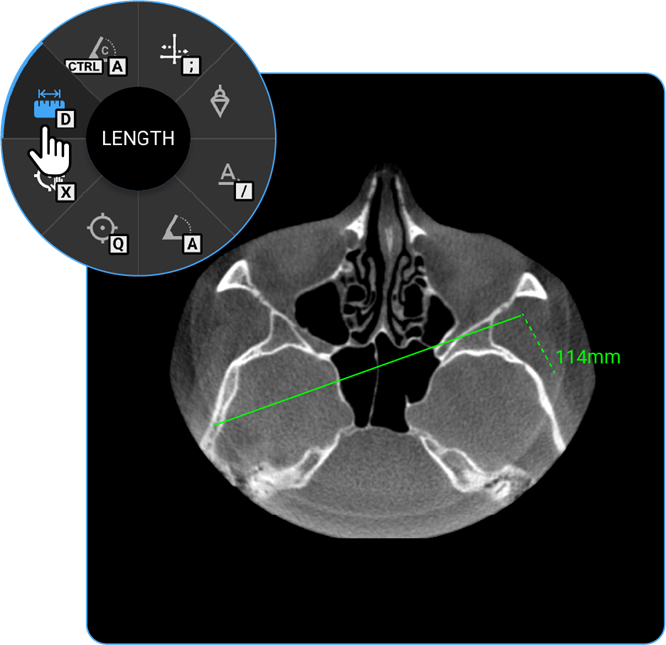

How Do I Measure Length?

- Usage: Measure distance between two points.

- Hotkey: Press D.

- Clinical Utility: Helps measure anatomical structures or lesion sizes.

- Locate the Length tool on the wheel and click on it to calculate the distance between two points on the image, useful for measuring anatomical structures.

- Length: Locate the Length tool on the wheel and click on it to calculate the distance between two points on the image, useful for measuring anatomical structures.